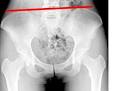

Bascule du bassin - Dfinition - Sant-Mdecine La bascule du bassin est un phnomne frquent qui se caractrise par l inclinaison du bassin. Discopatie L5S- Vulgaris Mdical juil. Bascule pelvienne gauche et jambe courte droit - Accidents. Bonjour, j ai ans je souffre d une bascule pelvienne de 15mm accompagnee d un symdrome scoliotique suivi de douleurs chronique du bassin a la cuisse je.

J ai une bascule pelvienne de mm et un pincement en LS1. Une inclinaison pelvienne provoque de nombreux problmes et des douleurs dans le dos ou sur les membres et doit donc tre strictement. Les exercices majeurs - GYM OSTH Un dsquilibre pelvien se rpercute sur l ensemble du corps.